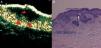

Carcinoma basocelular infiltrativo. A) Modo B (20Mhz) corte transversal. Se observa una imagen hipoecoica heterogénea subepidérmica (estrella roja), con bordes irregulares aunque bien definida con numerosas prolongaciones hipoecoicas a dermis subyacente (flechas rojas), indicativas de infiltración. La lesión además está ulcerada, como se aprecia por la interrupción de continuidad de la epidermis subyacente (U). B) Imagen histológica del tumor (H-E×4).

De hecho, si analizamos por separado el subgrupo de CBC superficiales (tabla 2B) se observa que el VPP obtenido para la ECO fue del 93,33%, similar al obtenido por el punch. Esto indica que en más de 9 de cada 10 casos en los que la ECO cutánea diagnostica un subtipo superficial (con hallazgo ecográfico de patrón hipoecoico subepidérmico aplanado, bien definido y sin prolongaciones hipoecoicas a dermis subyacente [fig. 2]) lo hace de forma correcta, y por tanto realizaría una adecuada clasificación histológica, al igual que la biopsia, de cara a seleccionar un tratamiento no invasivo.